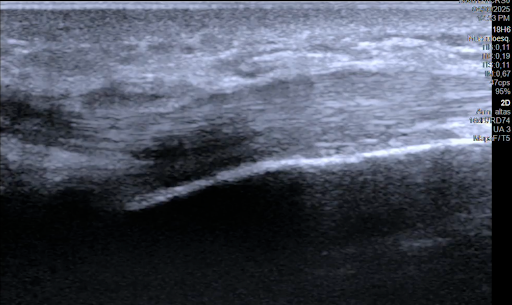

¿Dolor súbito en el codo y pérdida de fuerza al doblar el brazo o girar el antebrazo? Puede tratarse de una rotura del bíceps distal. Con técnicas quirúrgicas mini invasivas, es posible reparar el tendón con incisiones mínimas, menor dolor y una recuperación más rápida.